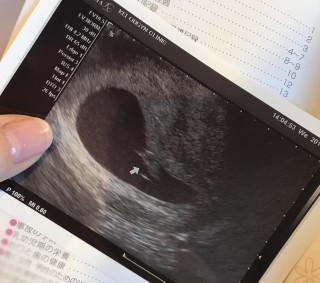

凍結胚移植3回目でやっと妊娠。5週0日で胎嚢確認出来て6週0日で心拍確認。 7週入ってからつわりが来て7週3日で14.2㍉♪ 心拍も150で順調との事♡ 乳ガンで左乳房全摘出からの不妊治療。右おっぱいだけパンパンです!